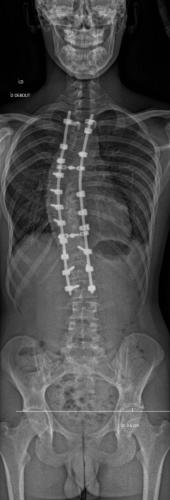

Images de scolioses opérées 16 janvier 202418 janvier 2023 par Damien Scoliose Thoracique 3 Scoliose thoracique D - Cliché pré-opératoire de Face Scoliose thoracique D - Cliché pré-opératoire de Profil Scoliose thoracique D - Cliché post-opératoire de Face Scoliose thoracique D - Cliché post-opératoire de Profil Aspect de la cicatrice à distance de l'intervention